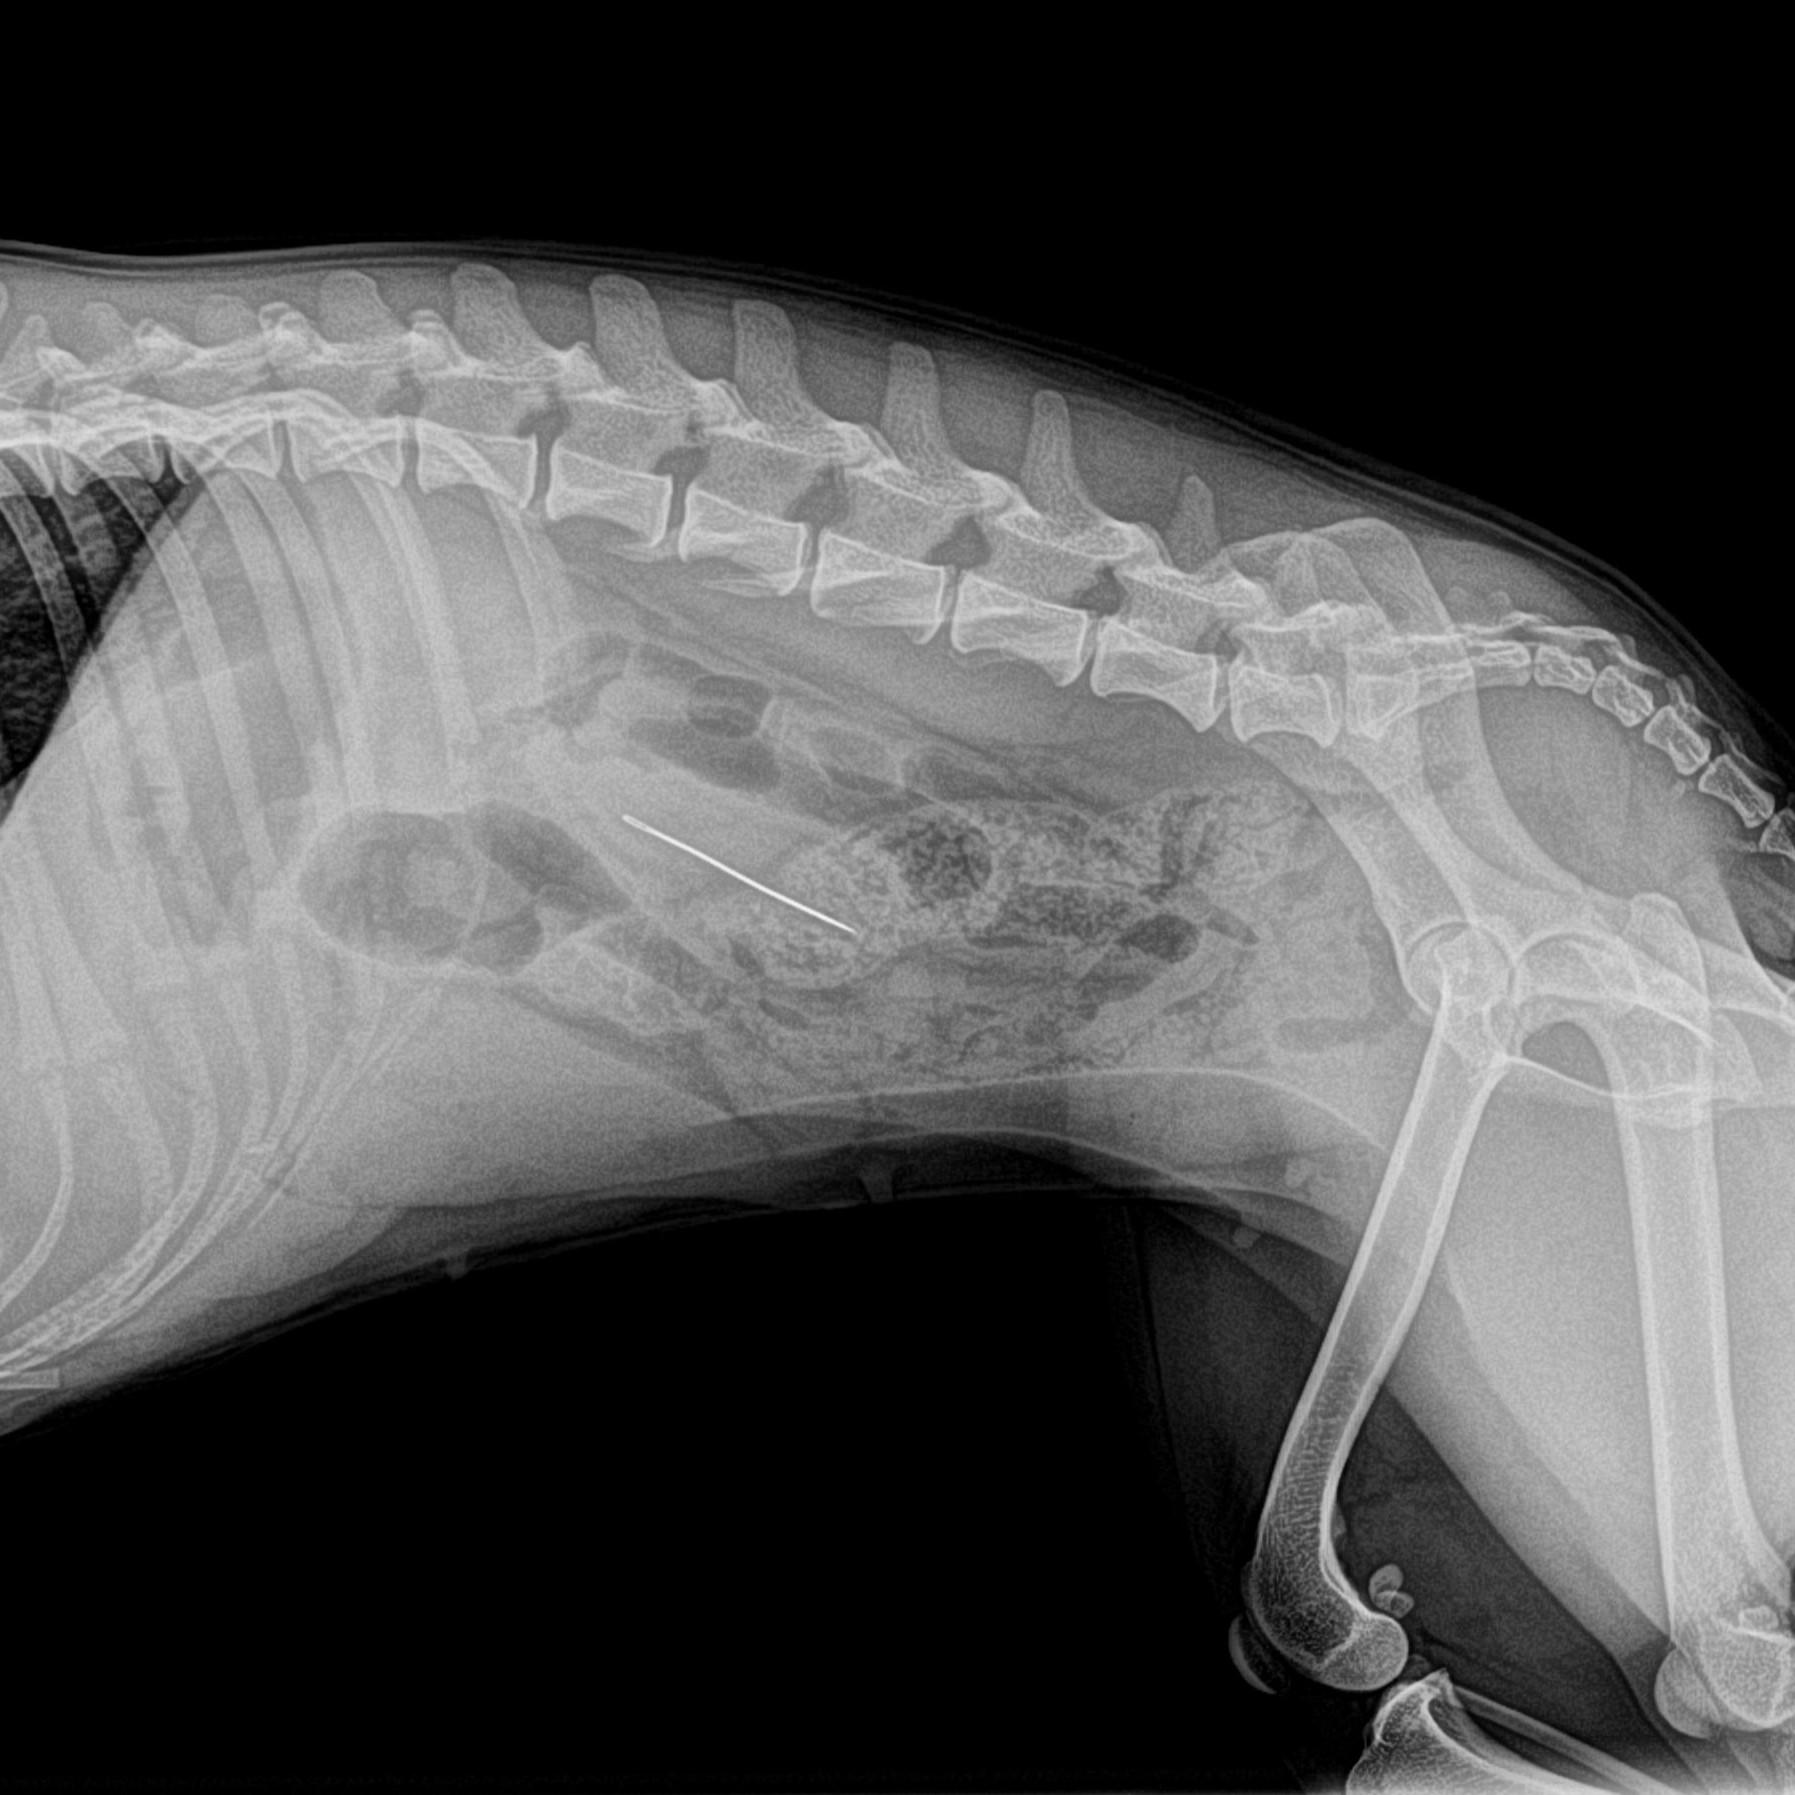

Radiographie abdominale

Elle permet de visualiser différents organes de l'abdomen. Elle est également utilisée pour la recherche par exemple de corps étrangers dans le tube digestif. Pour une meilleure visualisation de l'ensemble du tube digestif, il est parfois nécessaire d'utiliser des produits de contraste.

abdomen de chienne avec corps étranger